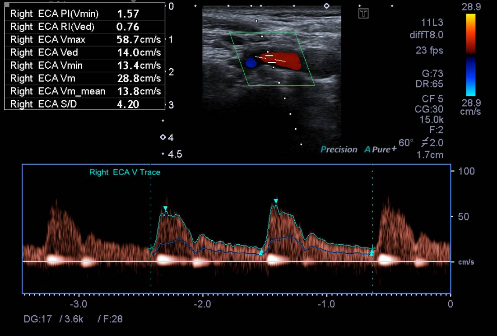

Sonar

Ultrasound imaging, also called sonography, uses sound waves to produce ultrasound images of the inside of the body. An instrument called a transducer emits high-frequency sound, inaudible to human ears, and then records the echoes as the sound waves bounce back to determine the size, shape, and consistency of soft tissues and organs. It is used to help diagnose the causes of pain, swelling and infection in the body's internal organs, joints and tendons. Doppler ultrasound is used to evaluate the arteries and veins to diagnose obstructions or blood clots also vascular malformities. Ultrasound is safe, noninvasive, and does not use ionizing radiation. Ultrasound is useful for guiding biopsy procedures.